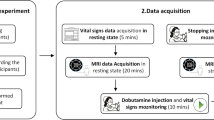

[15O]water PET with ACZ challenge: data acquisition, processing, and analysis

PET data acquisitions and analyses were performed as previously described using a semi-quantitative approach to avoid the need for arterial blood sampling [7, 17]. In brief, after a low-dose CT for attenuation correction, four 4-min scans at an inter-scan interval of 10 min were acquired per patient on a Philips Gemini TF64 PET/CT (n = 2; until 12/2017) or a Philips Vereos digital PET/CT system (n = 20; from 01/2018 onward; Philips, The Netherlands) after intravenous slow-bolus (3 s) injection of 300 MBq [15O]water (10-ml volume). Two scans were done before, and two scans at 5 and 15 min after a 5-min infusion of ACZ (1000 mg in 10 ml; n = 2 received 800 mg because of low body weight of 53 and 55 kg). PET data sets were reconstructed into a dynamic sequence of 30 frames (18 × 5 s, 9 × 10 s, and 3 × 20 s) using a vendor-specific 3D iterative reconstruction. For simplified voxel-wise calculation of CPR maps, all scans of each subject were corrected for possible head motions and integrated over 60 s after arrival of the tracer in the individual’s brain (according to a whole-brain time-activity curve). After averaging the two integral scans before and after ACZ administration and applying an empirical whole-brain segmentation (mask threshold: 18% of image maximum), voxel-wise estimates of CPR were created by calculating the signal change (%) in each voxel from baseline to ACZ stimulation. These parametric images were smoothed (Gaussian filter, 12-mm FWHM) and masked (see above) to give the final CPR maps. We used a customized “UCLA 2” color scale for display of the CPR maps. For VOI analyses (see MRI data preprocessing), CPR maps were spatially normalized using a PET template in MNI space (provided in Statistical Parametric Mapping (SPM 12, http://www.fil.ion.ucl.ac.uk/spm/)) and baseline integral images for estimation of individual normalization parameters. The commercial software packages PMOD (version 3.7; PMOD Technologies LLC, Switzerland) and MATLAB (The MathWorks, Inc., Natick, MA, USA), as well as the freely available SPM 12 were used for the aforementioned analyses.

The effect of time delay correction was examined for the entire cohort, as well as in subgroups. We therefore divided the bh-fMRI data sets into three subgroups based on their BOLD signal time-courses without time shift correction: (1) data sets showing negative CVR-values, indicating inverse signal response (so-called steal phenomenon) in at least one VOI, (2) data sets with territorial time delay of at least 3 s relative to the cerebellum in at least one VOI, and (3) data sets with neither steal phenomenon nor territorial time delay between the evaluated VOIs (see Fig. 2).

Exemplary averaged bh-fMRI BOLD signal time-courses of each VOI of a one data set with steal phenomenon (visible in the territory of the left parietal MCA), b one data set with territorial time delay (visible in the territories of the right frontal and parietal MCA), and c one data set with neither steal phenomenon nor territorial time delay. The cerebellar signal time-courses are shown in red and the other VOIs’ signal time-courses in blue. Superimposed on each signal time-course is the mean cerebellar signal time-course in green. The duration of each averaged cycle was 69 s